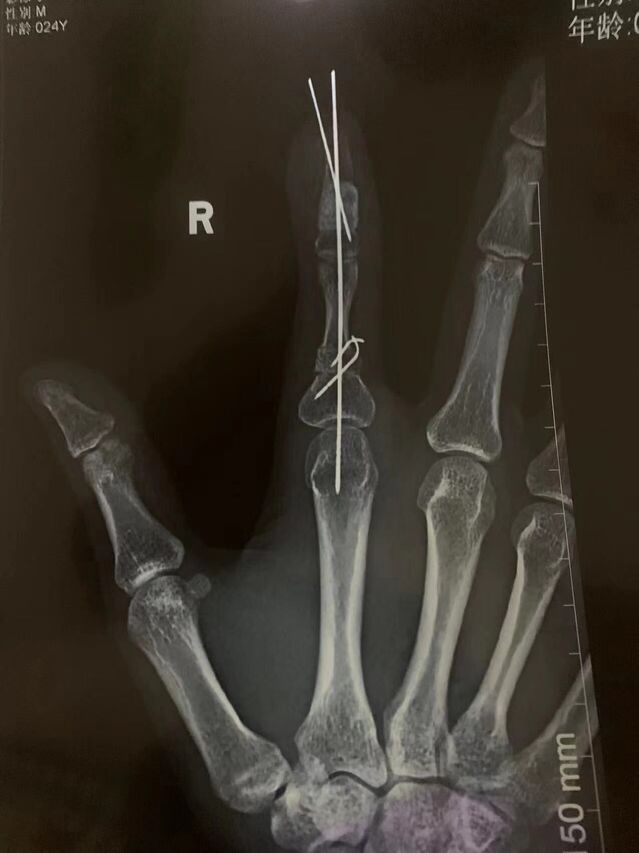

下面是一例示指再造,术后一年10个月随访

微信图片_20230930083837.jpg 微信图片_20230930083849.jpg 微信图片_20230930083851.jpg 微信图片_20230930083851_1.jpg

术后骨折愈合良好